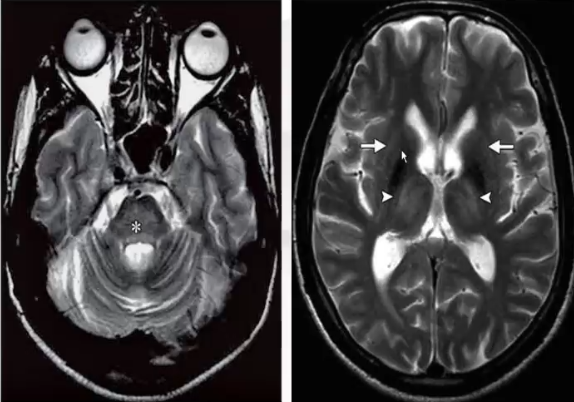

❖ 典型的病变为脑桥中央病变(脑桥中央的脱髓鞘),其余部位的改变可见于基底节、丘脑和白质(脑桥外髓鞘溶解)。

❖ MRI表现:病变区的T1低信号,T2高信号,增强不常见,可见弥散降低,DWI高信号。